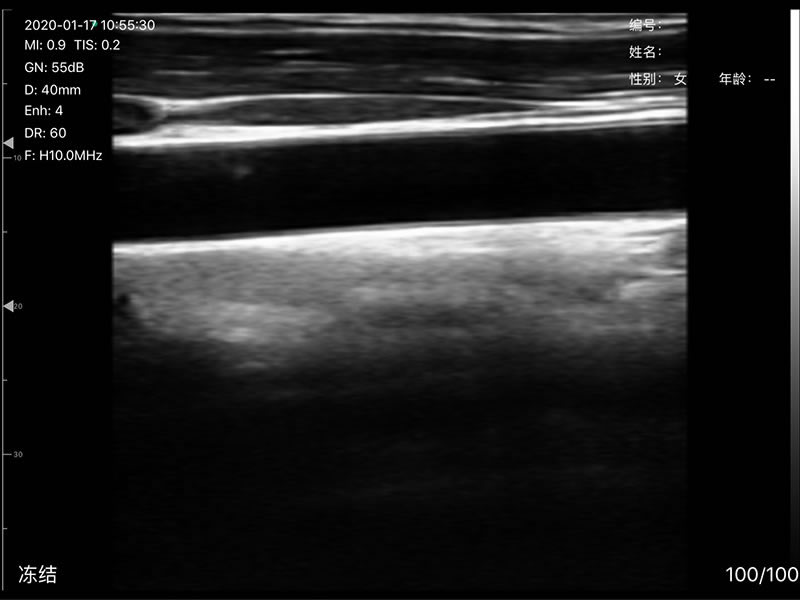

L40 Linear probe 7.5MHz/10.0MHz

• Display Depth: Convex 90/160/220/305mm, Linear 20/40/60/80mm

• Scan angle and width: convex 60°, Phasedarray 80°, linear 40mm